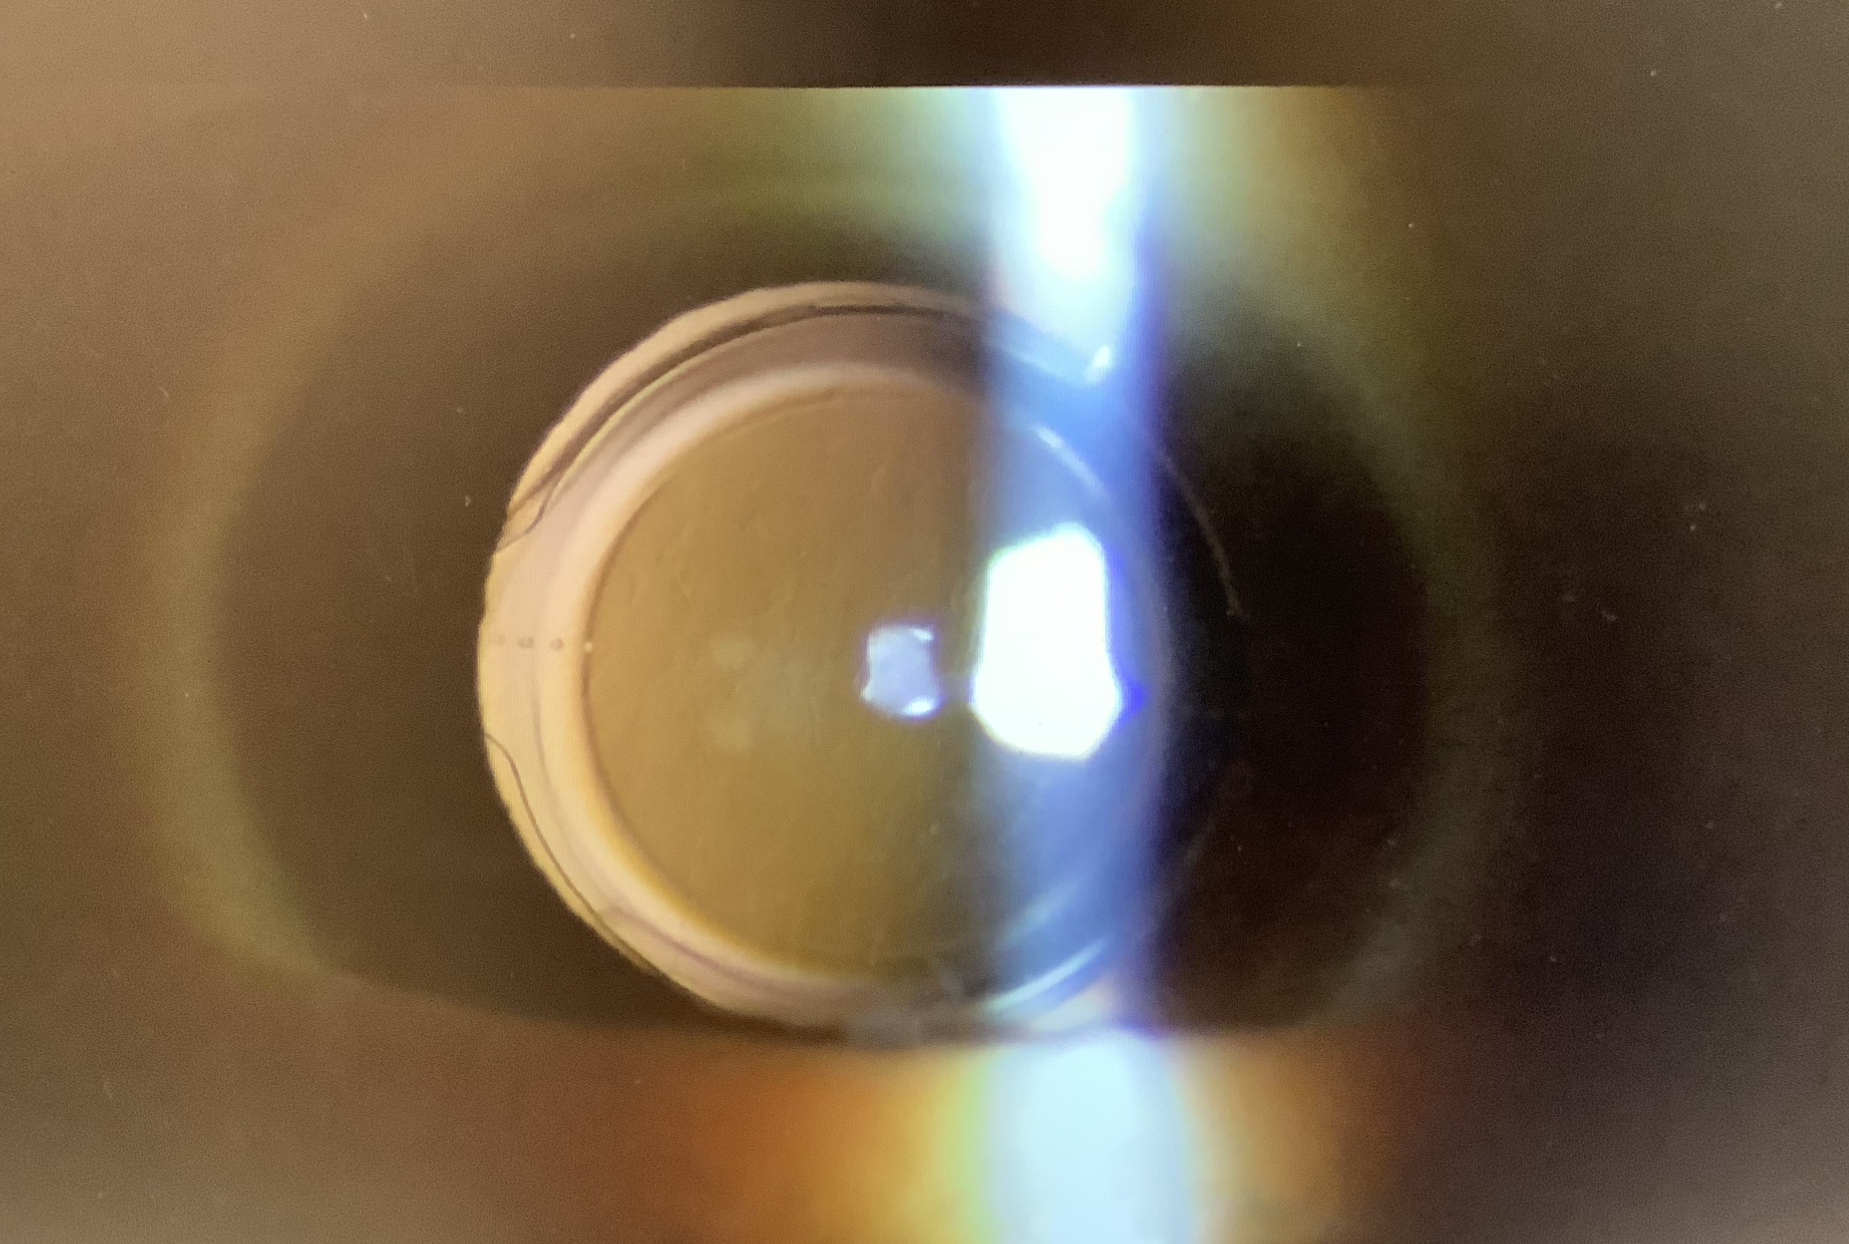

今日の手術は、白内障18件、内反症1人、霰粒腫1人(7歳女の子)でした。

今日の外来では、2か月前に白内障の手術を受けた方から、『もう少し遠くを見えるようにしたい』というご希望で、レンズ交換の予定を立てることとなりました。現在の状態は-0.5Dの近視で遠方の裸眼視力が0.9ですが、レンズの度数を換えるとしたら1段階になるかと思います。この1段階遠方寄りのレンズに換える操作自体は十分可能ですが、これでぴったり遠方に合わせられるか?というのは、正直、やってみないと分からないという答えになってしまうかと思います。レンズを交換する手術で結果に影響するのは、もちろん、レンズの度数が最も大きな要因になりますが、その他、眼に入れる切開創による乱視の変化(惹起乱視)、チン小帯への負担による度数計算の精度への影響などが考えられ、それらのトータルの結果で見え方が決まってきます。そのため、眼内レンズの度数の差が小さい場合は、他の因子の影響の方が大きくなってしまい、思ったようにピントが変わらない可能性がある訳です。サッカーでいうと、大きくサイドチェンジをするパスだと、多少誤差があっても明らかな違いが出ますが、小刻みなパス回しのような近いパスだと、あまり変わりがないような感じがしてしまうようなイメージです(ちょっと分かりにくい例えでした、、、)。近めのピントを遠くに変えるとか、ピッタリ遠くが見えているのを、中間くらいに合わせるといった、ある程度、大きな変化を作るには、眼内レンズ交換は十分な効果を見込めますが、ほんの少しを微調整する眼内レンズ交換は、あまり変わらない可能性があるということを承知の上で、それでもレンズを入れ換えたいと思った場合に受けていただくことが必要かと思います。今日の患者さまにもその旨は、十分説明させて」いただき、その上で、ご希望をいただいたとので、手術を予定させていただきました。もちろん、あまり変わらない可能性があるといっても、ご希望の見え方を実現できるように最大限の手術はしたいと思っていますので、よろしくお願いいたします。